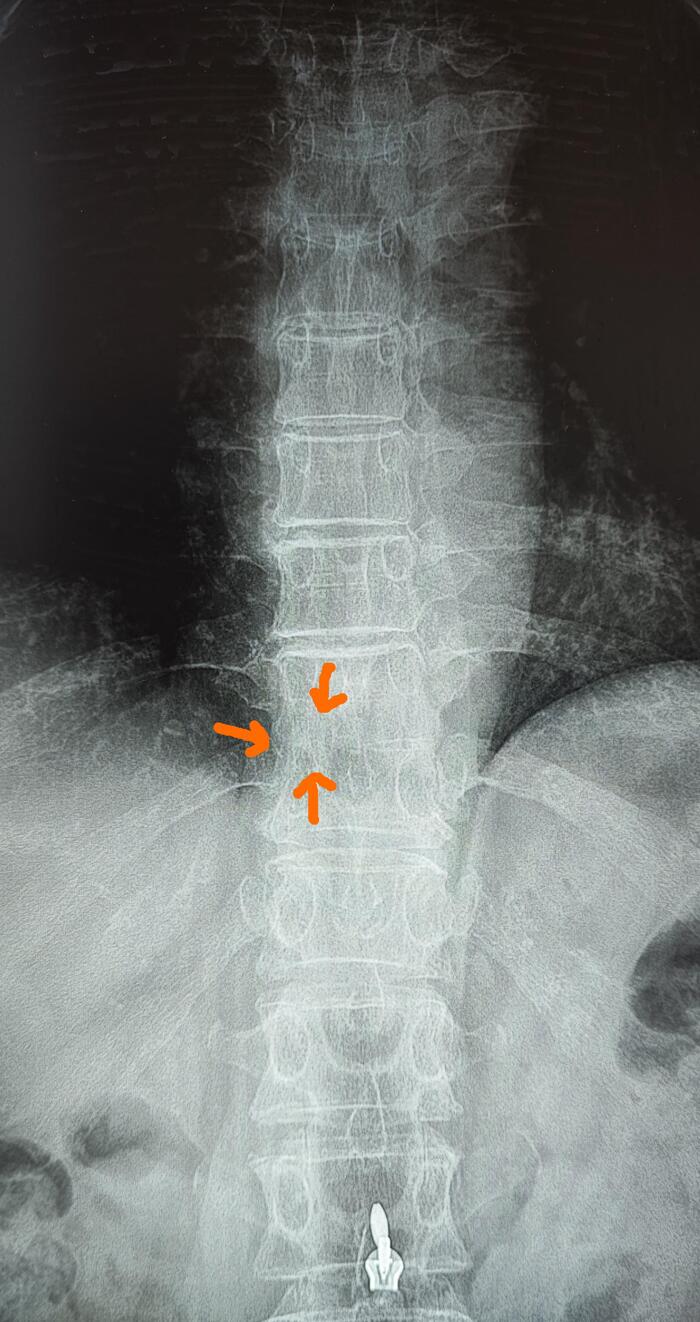

На МРТ- снижение высоты передних отделов тел Th6,7,8 позвонков(клиновидная деформация).

На Р-грамме грудного отдела позвоночника(стоя) в боковой проекции, визуализируется гиперкифоз грудного отдела позвоночника 4 ст. по Коббу. Аналогично с данными МРТ , снижение высоты передних отделов тел Th6,7,8 позвонков(клиновидная деформация).

На Р-граммах грудного, поясничного отделов позвоночника определяется S -образное искривление оси позвоночника, с левосторонней дугой, вершиной на Th10,угол девиации 20 град., правосторонней дугой, вершиной на L2, углом девиации 15 град.

Итоговый диагноз: Патологический гиперкифоз грудного отдела позвоночника 4 ст. по Коббу. Клиновидная деформация тел Th6, Th7, Th8 позвонков, как следствие перенесенной остеохондропатии, соответствует болезни Шейермана-Мау.S-образный сколиоз 2ст.Остеохондроз грудного, поясничного отделов позвоночника.